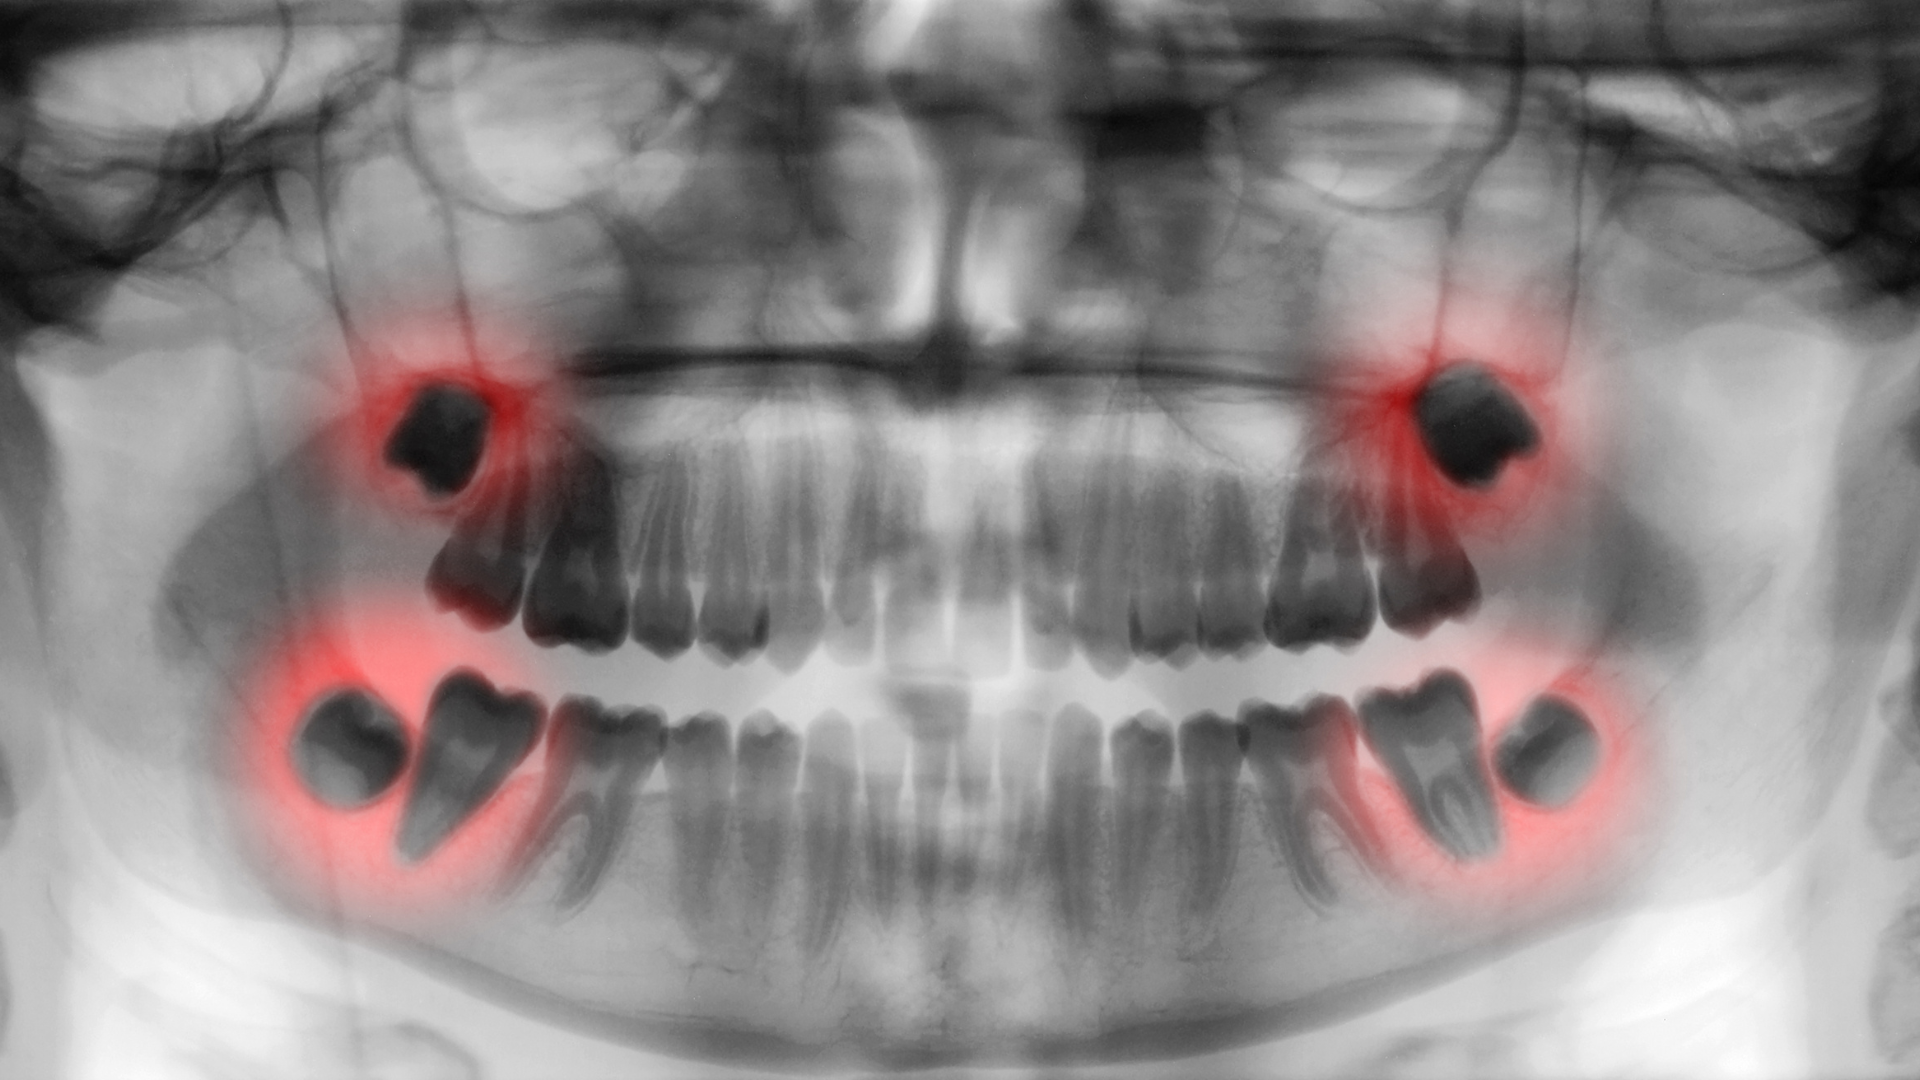

Tiêu xương hàm và bệnh nha chu

CT răng cho phép:

- Đánh giá mức độ tiêu xương theo chiều sâu và chiều ngang.

- Xác định vùng xương còn đủ điều kiện giữ răng.

- Hỗ trợ lập kế hoạch điều trị nha chu hoặc phục hồi.

Điều này rất quan trọng trong việc quyết định tiên lượng răng và kế hoạch phục hình sau điều trị.